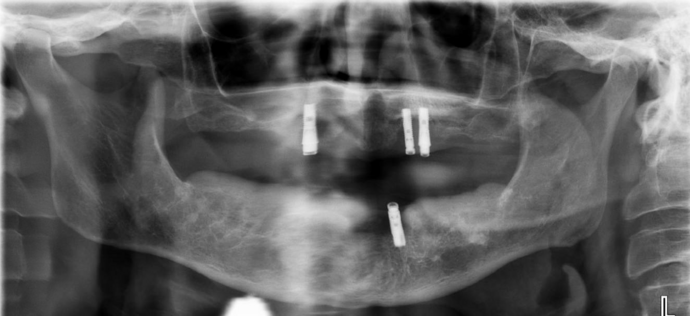

This busy professional unfortunately had lost all his teeth and then had implants placed for snap on dentures. The implants started failing after a few years and experienced bone loss. Patient was previously told my multiple dentists that he was not a candidate for dental implants. Patient was always unhappy with his snap on dentures and desired a permanent solution. The old implants were removed and Dr Bidra placed new implants in the upper and lower jaw and installed permanent teeth in the same day. After 4 months of healing, new zirconia permanent teeth were installed.

Procedures : extractions, failing snap on dentures, new implants, All on 4 , Teeth in a day, no bone grafting and full mouth reconstruction with monolithic zirconia bridges.